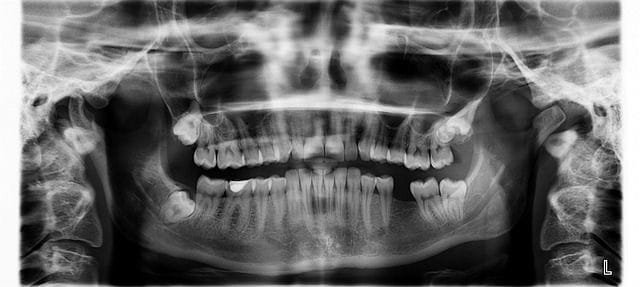

Número de molares en la edad adulta

Una persona adulta puede llegar a tener hasta 12 muelas permanentes, repartidas de la siguiente forma:

Tres por cada sección de la boca: parte superior e inferior, lado derecho e izquierdo

En total: 3 x 4 = 12 piezas

Estas incluyen las conocidas muelas del juicio. No todos las desarrollan, por lo que es común tener únicamente 8 dientes molares funcionales.

Clasificación de los molares

Dentro de los dientes posteriores permanentes, encontramos tres tipos principales:

| Tipo de muela | Cantidad total | Función |

|---|---|---|

| Primer molar | 4 | Inicia la trituración |

| Segundo molar | 4 | Complementa la masticación |

| Tercer molar (cordal) | 4 | A veces ausente; puede extraerse |

Las llamadas “cordales” o muelas del juicio aparecen, si lo hacen, entre los 17 y 25 años.